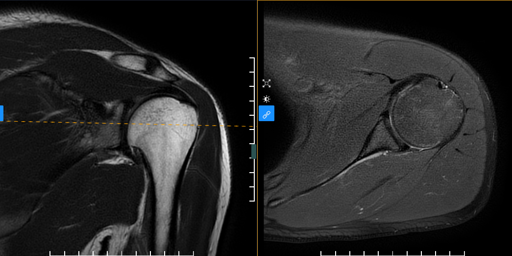

Chụp cộng hưởng từ khớp vai là gì? giải đáp thắc mắc cùng...

Trong hệ vận động khớp vai là một khớp có vai trò quan trọng. Khả năng vận động của khớp vai lớn bởi khớp vai được cấu tạo có nhiều cấu trúc. Các cấu trúc cấu tạo nên khớp vai kể đến như xương, sụn khớp, dây chằng, thần kinh, cơ…Bởi vậy khi thăm khám khớp vai cần có một công cụ chính xác và chi t...